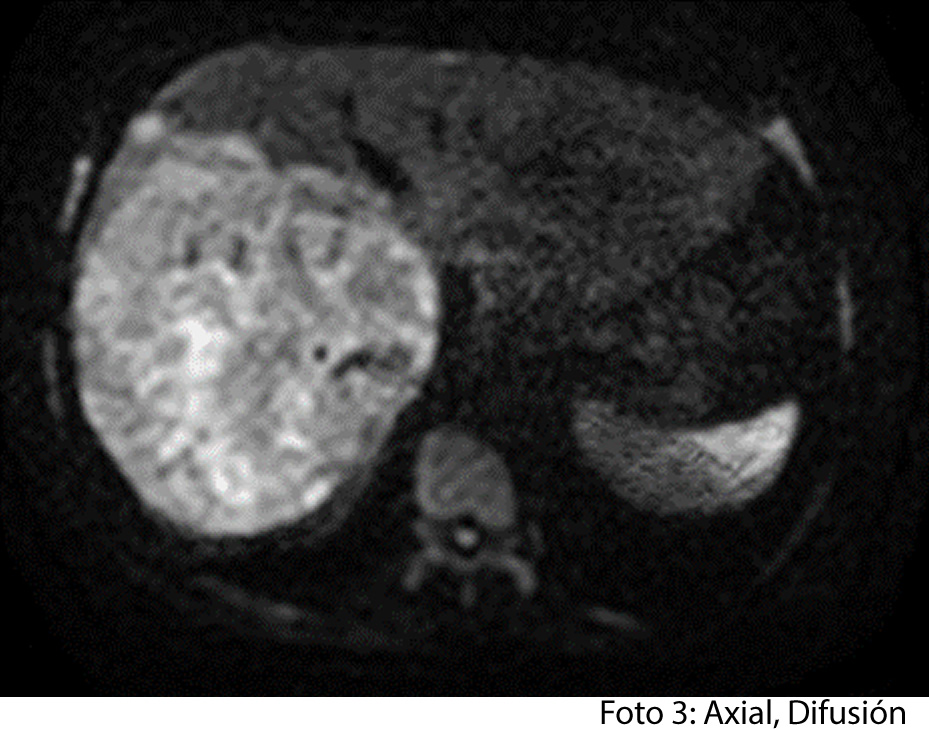

HALLAZGOS IMAGENOLOGICOS

• HEPATOCARCINOMA FIBROLAMINAL QUE COMPROMETE TODO EL LÓBULO DERECHO DEL HÍGADO

Es un método utilizado en el cual podemos observar una gran masa localizada en los segmentos del hígado también se puede medir el diámetro de la masa, el hepatocarcinoma también puede presentar focos hemorrágicos y además podemos captar de manera heterogénea el medio de contraste intravenoso. En los hepatocarcinomas podemos ver obstruyendo parcialmente la vena porta. Adenomegalias los cuales nos indican Los hallazgos como primera posibilidad diagnóstica, carcinoma hepatocelular fibrolamelar (CHC-FL).